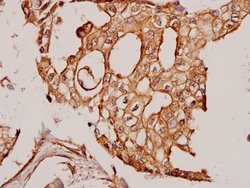

Invitrogen™ Cortactin Polyclonal Antibody

Brand: Invitrogen™ PA586614

Cortactin (Cttn) is a ubiquitous actin-binding protein that was originally identified as a substrate for Src. It contributes to the organization of the actin cytoskeleton and cell shape. Cortactin also plays a role in the formation of lamellipodia and cell migration. It is accumulated in peripheral, actin-enriched structures of cells suggesting that cortactin facilitates actin network formation. Cortactin has four major domains of interest the N-terminal acidic (NTA) and tandem repeats domains and the C-terminal proline-rich and SH3 Domains. NTA associates with the Arp2/3 and WASP complex at F-actin branches. Cortactin is involved in promoting cell motility and invasion, including a critical role in invadopodia, actin rich-subcellular protrusions associated with degradation of the ECM by cancer cells. Cortactin is phosphorylated by src family kinases at Y421, Y466, and Y482 and S405 and S418 that are phosphorylated by Erk family kinases.

| Immunohistochemistry (Paraffin) | |

| Synthetic peptide, corresponding to amino acids 382-432 of Human Cortactin. | |

| Human, Mouse, Rat | |